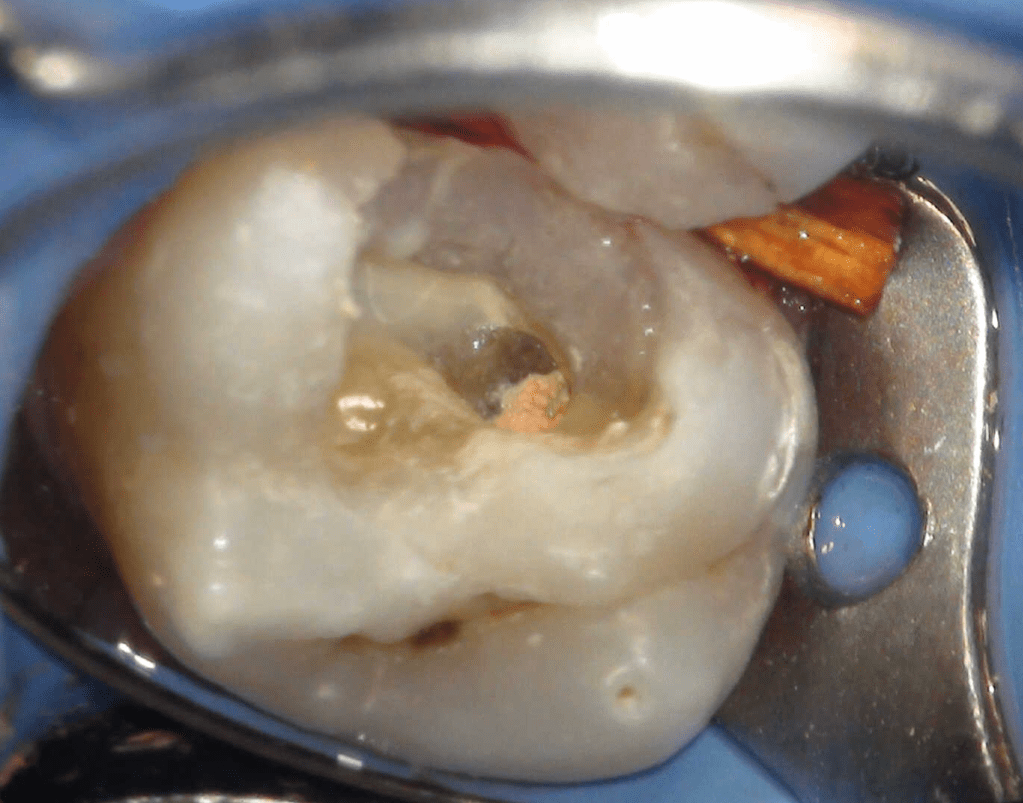

Pulpotomía biodentine + reco preendio